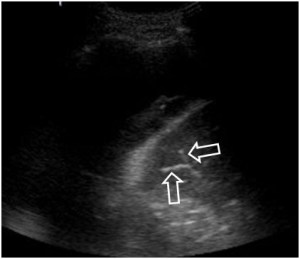

SIGNO DE LA BURBUJA DE AIRE

Cuando existe una aparente elevación del hemidiafragma izquierdo pero la burbuja gástrica permanece en su sitio, con el consiguiente aumento de distancia entre la burbuja gástrica y el aparente diafragma, hay que sospechar derrame subpulmonar y no elevación real del hemidiafragma. La fotografía muestra el signo; la flecha negra señala la burbuja gástrica; las flechas rojas marcan el aparente diafragma.

La imagen localizada permite ver mejor, además, el pinzamiento del seno costofrénico izquierdo por el derrame (flecha).